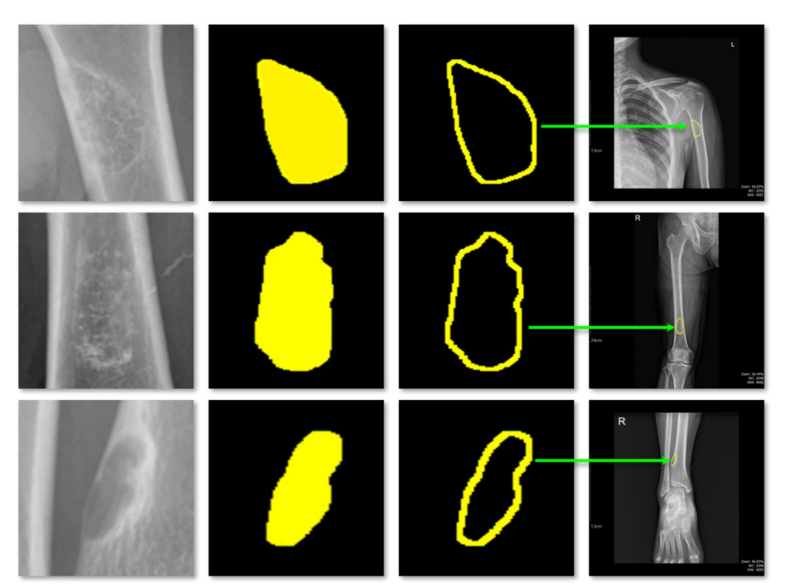

The framework trains a U-Net model using a specially constructed dataset that includes both original and wavelet-enhanced images. This approach significantly improves segmentation accuracy, ensuring reliable identification of tumor boundaries and shapes. The model’s consistent performance demonstrates its suitability for clinical applications.

Quantitative Tumor Measurement

FusionX-BBTNet automatically extracts the X-ray scale bar and converts pixel lengths into real-world measurements. It calculates tumor width, height, and area using bounding box dimensions and pixel counts. These values are displayed directly on the output images, providing clear, interpretable results for clinical review. This process solves the common challenge of inconsistent or approximate tumor measurements in radiographic analysis.